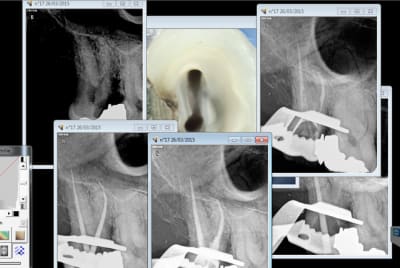

C'est pas une question de master ou pas. c'est une question d'avoir un microscope ou pas.

ici, impossible de trouver le canal dv sans microscope, c'est excessivement rare.

Capture d e cran 2015 03 26 18.34 - Eugenol

Capture d e cran 2015 03 26 18.40 - Eugenol